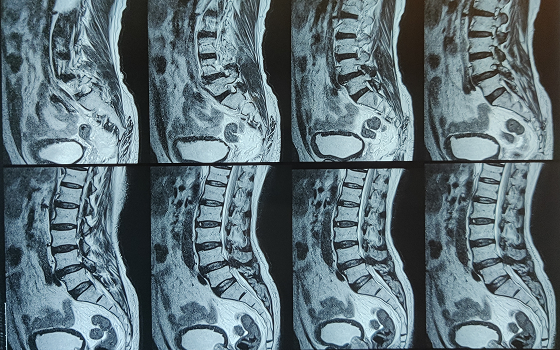

Dr. Somashekar D is an experienced spine surgeon in Bangalore. He is currently practising as a Consultant - Spine Surgery at Manipal Hospital Jayanagar, Bangalore. With nearly 10+ years of expertise in spine care, Dr. Somashekar has established himself as a highly skilled spine surgeon, contributing to over 1,500+ spine surgeries independently, ranging from simple decompressions to complex spinal reconstructions. His practice is deeply rooted in precision-based techniques and evidence-guided clinical protocols, ensuring both safety and long-term functional outcomes for his patients. He is a top spine surgeon in Jayanagar.

We offer comprehensive treatment for spine issues that is on par with any leading spine center worldwide. Our services encompass both non-surgical and surgical treatments tailored to address your specific condition. Our expertise covers a wide range of spine surgeries, including minimally invasive spine surgery, cervical spine surgery, scoliosis surgery, and complex spine surgeries.

Covers a wide range of spine surgeries, including complex spine surgeries.